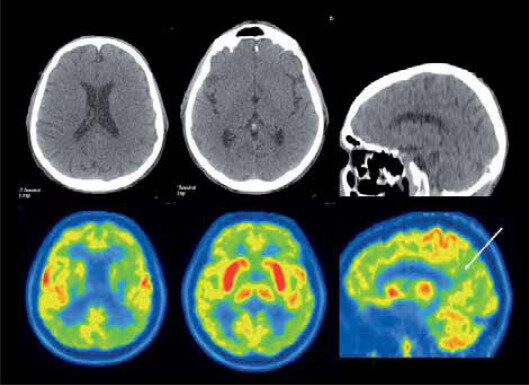

Paul Lauterbur combina la idea del gradiente con la idea del escáner de tomografía computada para realizar varias proyecciones y reconstruirlas para obtener la primera imagen por resonancia magnética.

• RESONANCIA MAGNÉTICA: Primera imagen

RESONANCIA MAGNÉTICA: Primera imagen

Mansfield y sus colegas de Inglaterra publican la primera imagen de un dedo humano obtenida por resonancia magnética.

• RESONANCIA MAGNÉTICA: Variaciones en oxigenación

RESONANCIA MAGNÉTICA: Variaciones en oxigenación

Seiji Ogawa detecta variaciones en la oxigenación del tejido local al utilizar contraste dependiente del nivel de oxígeno de la sangre.